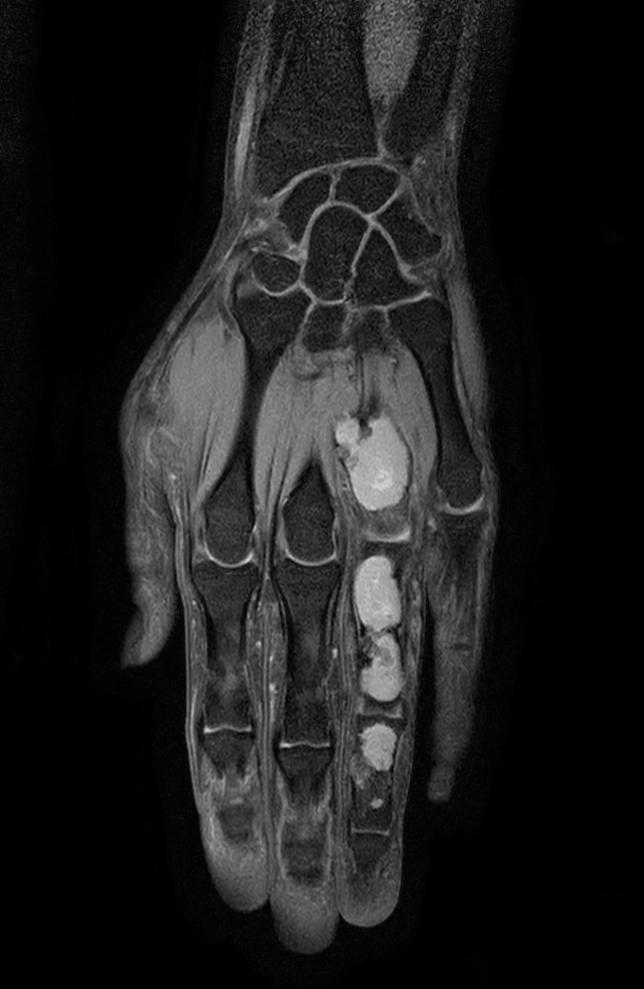

Axial T1w mDIXON XD TSE (Water only) (with gado)

Axial T1w mDIXON XD TSE (In Phase) (with gado)

Axial T1w mDIXON XD TSE (Partial FatSat) (with gado)